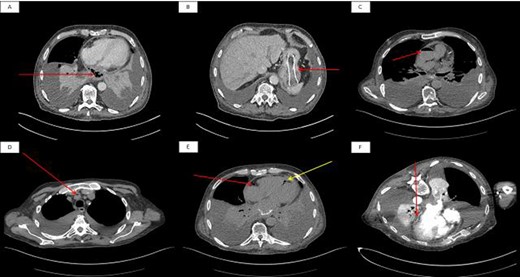

He presented to the acute medical service with a 2-week history of increasing lethargy and dyspnoea. An initial non-contrast enhanced computed tomography (CT) scan of his chest and abdomen (Fig. 1A and B) showed a lower oesophageal perforation and migration of the oesophageal stent into the stomach. Several hours later, the patient became somnolent and examination revealed left-sided hyper-reflexia with power 0/5 (Medical Research Council scale), left-sided facial weakness and inattention. A repeat CT scan revealed air in the ascending aorta, brachiocepahlic artery and right posterior descending artery (Fig. 1C, D and E, respectively). Conservative measures were taken including nursing in the Trendelenberg position, and a repeat CT scan with contrast was organized. This third scan showed dissipation of the air, but loss of the fat plane between the left atrium and oesophagus (Fig. 1F); this was suggestive of an oesophago-atrial fistula (OAF). The patient developed seizures and his conscious level declined. He was treated with palliative intent and died a few hours later.

Initial non-contrast enhanced axial CT scan of the thorax. (A): The arrow shows lower oesophageal perforation with cavity containing air and debris in the posterior mediastinum. (B): The arrow shows migration of oesophageal stent into the stomach. A second non-contrast enhanced axial CT scan of the thorax showed air in the ascending aorta (C), brachiocephalic artery (D) and (E) right coronary artery (red arrow) and posterior descending artery (yellow arrow). A final contrast-enhanced axial CT scan of the thorax (prone position) shows loss of the fat plane at the junction of the oesophageal tumour and left atrium.